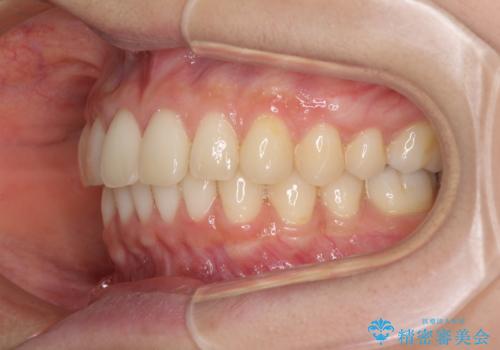

インビザラインによるディープバイトの改善

- 口元の前突感と深い咬み合わせ(ディープバイト)を気にして来院された患者様です。

インビザラインによる上下歯列の遠心移動(後方移動)と、それに伴う近心傾斜(前方傾斜)の改善により、口元の突出感とディープバイトを改善することとしました。

前歯のデコボコを最も気にしていましたが、咬み合わせが深く歯ぎしりが自由にできない点を指摘すると、常に食いしばってしまうことも悩みであることが分かりました。

咬合状態が大きく変化したため、治療後半では咬み合わせの位置が定まらなくなりました。上下の前歯に後戻り防止用のワイヤーを装着し、奥歯の咬合をフリーにしたことで1ヶ月ほどで咬み合わせが定まりました。